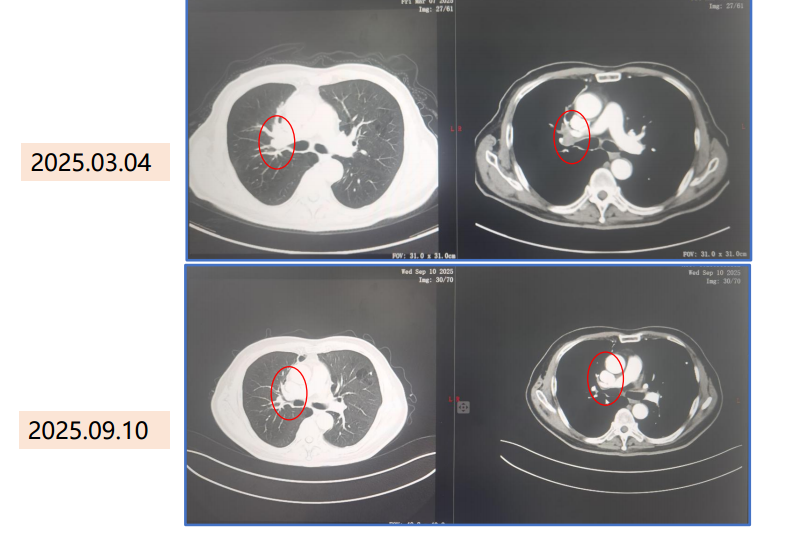

疗效评估:3周期新辅助治疗后,影像学对比显示病灶显著消退。

胸部CT对比(2025.03.04 vs 2025.09.10): 右肺门及纵隔病灶明显缩小,术前新辅助疗效评估为临床完全缓解(Clinical CR)。

2.png